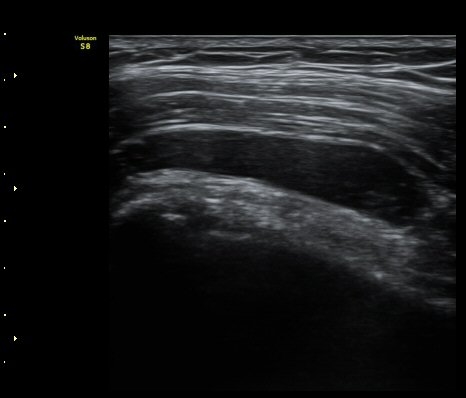

ÃÊÀ½ÆÄ °Ë»ç

¾î±ú À̵ιڱ٠Ⱦ´Ü¸é°Ë»ç¿¡¼­ ½ÉÇÑ Á¡¾×³¶³» ¼ö¾×Àú·ù°¡ °üÂûµÇÁö¸¸ ÆÄ¿öµµÇ÷¯

°Ë»ç¿¡¼­ Ç÷·ùÁõ°¡´Â °üÂûµÇÁö ¾Ê´Â´Ù(±×¸² 1, 2).   À̵ιڱ٠¾Æ·¡ Ⱦ´Ü¸é°Ë»ç¿¡¼­

°üÀý³» ¼ö¾×Àú·ù´Â ¶Ñ·ÈÇÏÁö ¾Ê´Ù(±×¸² 3). ±Ø»ó°Ç Á¾´Ü¸é°Ë»ç¿¡¼­ Á¡¾×³¶³» ¼ö¾×

Àú·ù°¡ °üÂûµÈ´Ù(±×¸² 4, 5). ±Ø»ó°Ç Ⱦ´Ü¸é À­ ºÎºÐ¿¡¼­ °æ¹ÌÇÑ ¼ö¾×Àú·ù¸¦ º¸ÀδÙ(±×¸² 6).